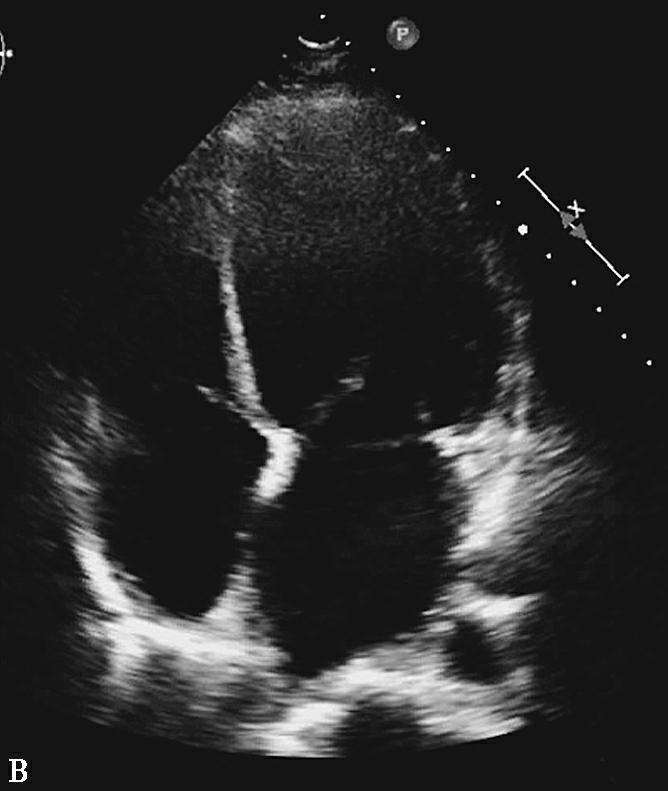

图2抗凝前后超声心动图对比

A图为入院心脏超声心尖四腔切面,可见右房内疑似血栓影,舒张期可进入右心室内;B图为抗凝治疗1周后复查,可见右房内血栓消失